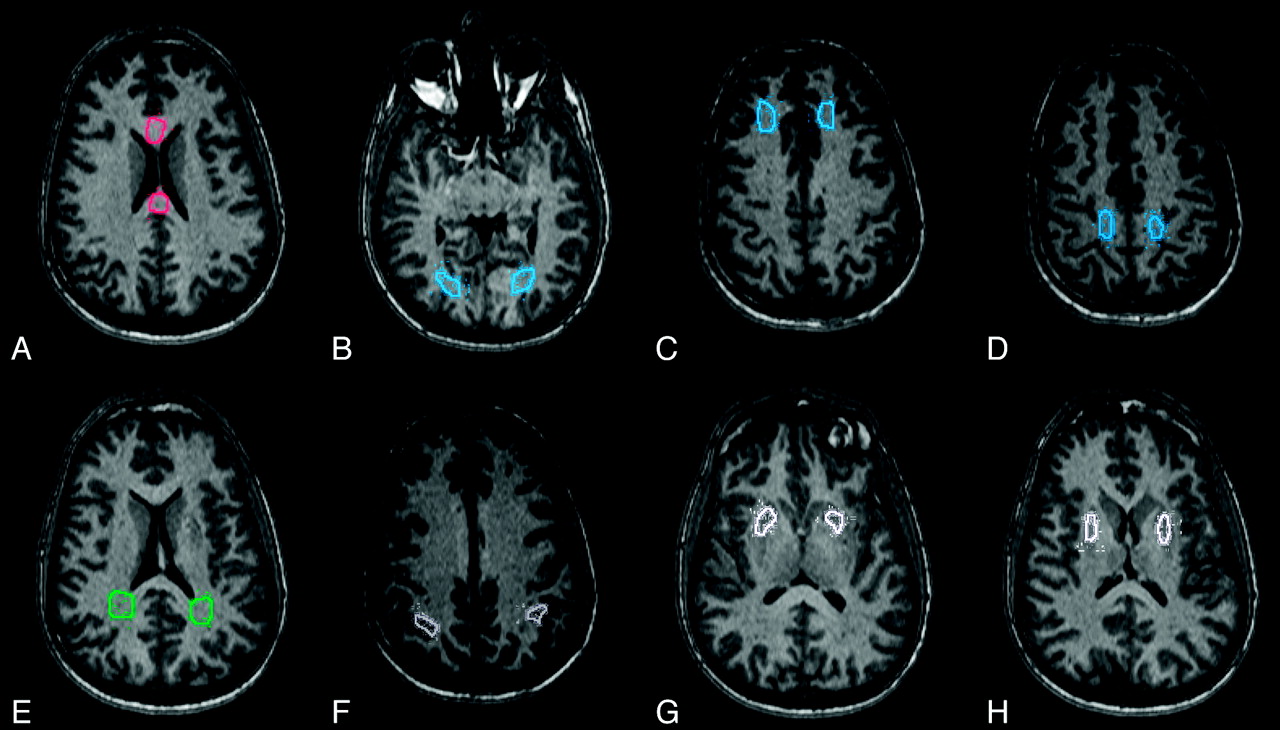

For each subject, 16 ROIs were drawn on the MPRAGE image from 1 of the magnets (Trio-1, Fig 1), which was used as a reference mask. The ROIs encompassed 5 major areas with differing anisotropic properties: 1) the corpus callosum (genu, splenium), 2) periventricular white matter (parietal, occipital), 3) deep white matter (frontal, parietal, occipital), 4) cortical gray matter (posterior parietal, occipital), and 5) deep gray matter (putamen). ROI volumes ranged from approximately 182 to 742 mm3, with the smallest ROIs located in the cortex. The final registration transformations (described above) were applied to coregister the reference ROI mask to each set of DTI images obtained from the other 4 centers. The ROIs were verified visually and adjusted manually to account for nonlinear distortions inherent to EPI data.

White and gray matter ROIs used for calculating DTI metrics in a single subject. Similar ROIs were used in the second subject. A, Anterior and posterior corpus callosum (red). B–D, Deep white matter (left and right occipital, frontal, and parietal, respectively; blue). E, Left and right periventricular white matter (green). F, Left and right cortical gray matter (gray). G and H, Left and right deep gray matter (putamen, white).